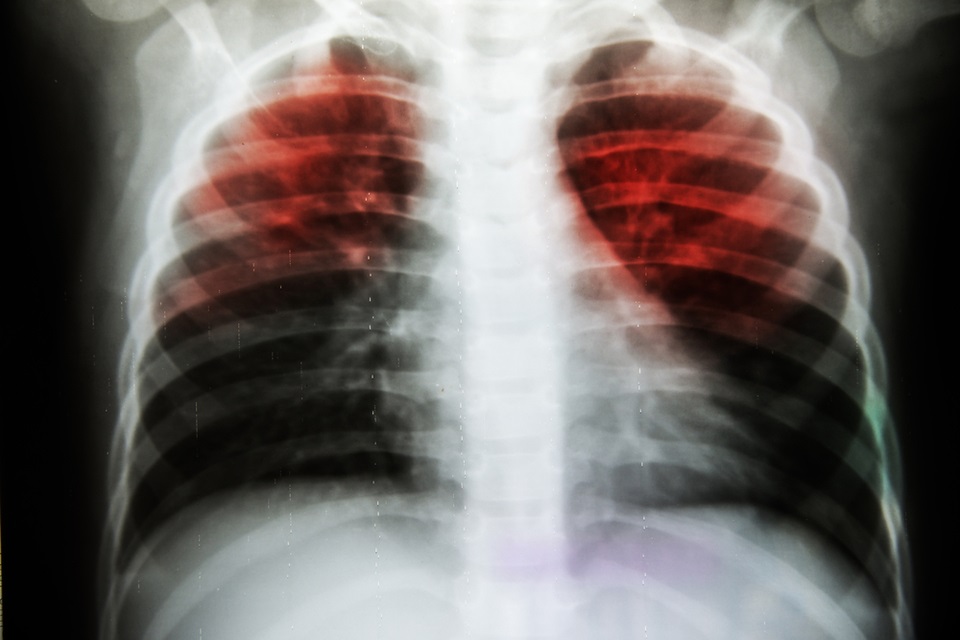

Tuberculosis is still a significant healthcare problem around the world and is the 10th most common cause of death worldwide, while almost half of TB patients also report suffering from depression as well.

Patients suffering from both of these conditions at the same time have significantly worse outcomes, as well as poorer adherence to treatment plans, which can cause further problems by raising the risk of TB transmission in communities, and the development of multi-drug resistant tuberculosis (MDR-TB).

Despite this there are no evidence-based treatments for people who have depression or anxiety as well as TB. This is a particular problem in countries such as Pakistan and Afghanistan, which both have high numbers of TB and MDR-TB cases.

To combat this, a research team co-led by Keele’s Professor Saeed Farooq is working to develop a programme of research, the key element of which is developing and testing a cognitive therapy treatment, called CONTROL, to improve the mental health of people who have TB and MDR-TB. In addition, the research team will also examine if it is an effective strategy for improving adherence to TB treatment plans, thereby improving public health by reducing the transmission of TB.